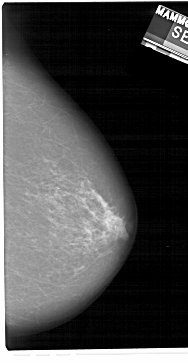

A_1181_1.RIGHT_MLO

RIGHT_MLO LINES 5491 PIXELS_PER_LINE 3181 BITS_PER_PIXEL 12 RESOLUTION 43.5 NON_OVERLAY